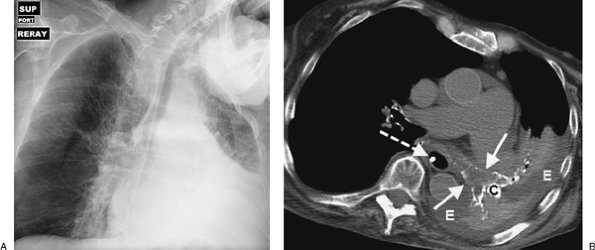

FIGURE 11-21. Left lung atelectasis. A: AP supine chest radiograph of an 82-year-old woman with dementia and respiratory distress shows nearly complete collapse of the left lung. Note mediastinal shift to the left. B: CT shows that the left main bronchus (solid arrows), lingular bronchus, and left lower lobe superior segment bronchus (all outlined by calcified walls) are airless and filled with low-attenuation material (mucus). There is a densely calcified left hilar lymph node (C). Pleural effusion (E) outlines the collapsed left lung. A feeding tube is present within the esophagus (dashed arrow).